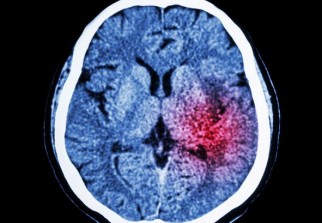

Les chercheurs de l'université du Minnesota à Minneapolis ont voulu comprendre l'impact des facteurs psychologiques sur les accidents vasculaires cérébraux. Ils ont mené une étude sur 6.700 adultes âgés de 45 à 84 ans qui ont répondu à des questionnaires précis sur leur niveau de stress, la dépression, l'agressivité et la colère. Ils ont analysé l'agressivité et la vision négative du monde des volontaires en évaluant leurs attentes et leurs motivations. Les participants ont été suivis pendant 11 ans. Aucun d'entre eux ne souffrait de maladie cardiaque. Au cours de cette période, 147 ont eu des attaques cérébrales et 48 un accident ischémique transitoire (l'AIT est un déficit neurologique soudain et temporaire. Ses symptômes cliniques durent moins d'une heure).

Les AVC aiment l'agressivité

Si la colère n'augmente pas les risques de subir un AVC, la dépression, le stress et l'agressivité semblent être liés à une augmentation d'accidents vasculaires cérébraux. En effet, les résultats de cette étude révèlent que les symptômes dépressifs augmentent de 86% le risque d'avoir une attaque cérébrale ou un AIT, que les individus qui sont chroniquement stressés ont un risque 59% plus élevé d'avoir ce type d'attaques. Les gens cyniques et agressifs sont eux 2 fois plus touchés par ces accidents.

«On se concentre tellement sur les facteurs traditionnels de risque, le niveau de cholestérol, la pression sanguine, la cigarette etc, et ils sont tous très importants. Mais une étude comme celle-là montre que les facteurs psychologiques doivent être aussi considérés», explique l'une des auteurs de l'étude, Susan Everson-Rose, professeur de médecine associée à l'université du Minnesota à Minneapolis.

«Compte tenu du vieillissement de la population, il est important d'examiner ces autres facteurs de risques. Car, l'AVC est une maladie qui touche majoritairement les personnes âgées « explique Susan Everson-Rose. Chaque année en France, 130 000 personnes sont victimes d'AVC, faisant 33 000 décès. Plus de 771 000 personnes d'entre elles en subissent encore les séquelles. C'est la 3e cause de mortalité après les cancers et l'infarctus du myocarde et la 2e cause de démence après la maladie d'Alzheimer.

3 personnes sur 4 ayant eu un AVC a plus de 65 ans.